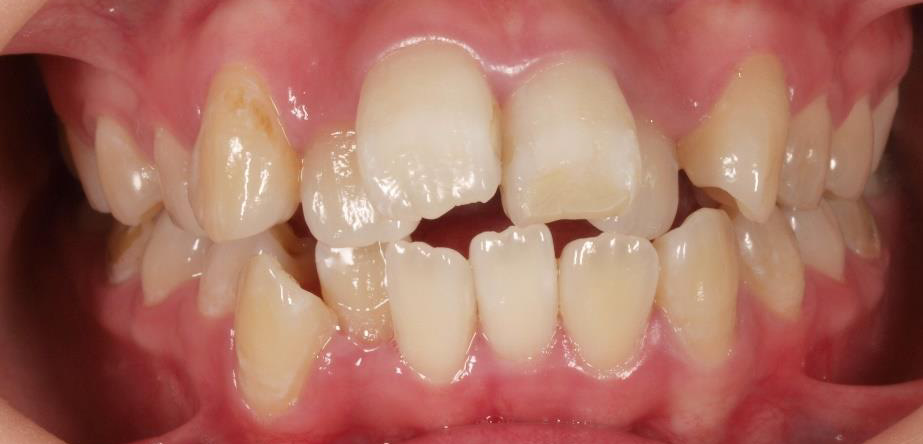

乱ぐい歯、でこぼこがとても酷い状態になります。歯が前後的に重なってしまっている、八重歯になっているなどがこのジャンルに入ります。

顎の大きさと歯の大きさのギャップが大きく、時には歯を抜かないと矯正治療ができない場合もあります。当院では治療期間が長くなるが抜かない治療方針など、一つの治療プランだけでなく、さまざまな可能性の治療方針を説明させて頂くよう心掛けております。こういった考え方はインフォームド・チョイスと言われ近年大切にされている考え方と言われております。

治療前

治療終了前